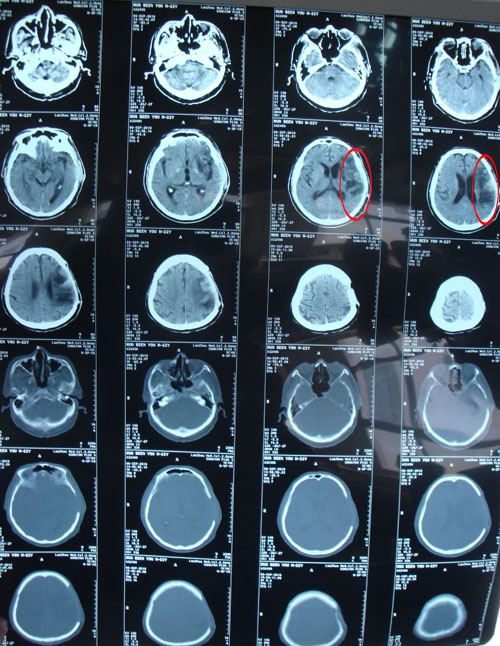

患者霍某某,男,71岁,主因发现右侧颈动脉狭窄2月入院。患者于入院前2月无诱因出现失语、口角偏斜、右上肢无力、无抽搐、无大小便失禁。急到兰州大学第二附属医院就诊。头颅CT示:左侧大面积脑梗塞。颈动脉DSA示:右侧颈动脉狭窄。行左侧颅内外动脉吻合术,并给予营养神经、降颅压、扩张血管等综合处理后出院。此次门诊以”右颈动脉狭窄”再次收入院。

头颅CT示:左侧大面积脑梗塞。

诊断:右颈动脉狭窄,左侧颞浅动脉—大脑中动脉吻合术后血流通畅,继发脑出血。此次复查颈动脉超声

该患者病例特点:老年男性,2月前行因大面积脑梗塞行左侧颞浅动脉—大脑中动脉吻合术后血流通畅,继发脑出血。此次复查颈动脉超声提示右侧颈内动脉狭窄(70%-99%);左侧颈总动脉狭窄(50%-69%)。为彻底治疗颈动脉狭窄病变,行颈动脉内膜剥脱术。